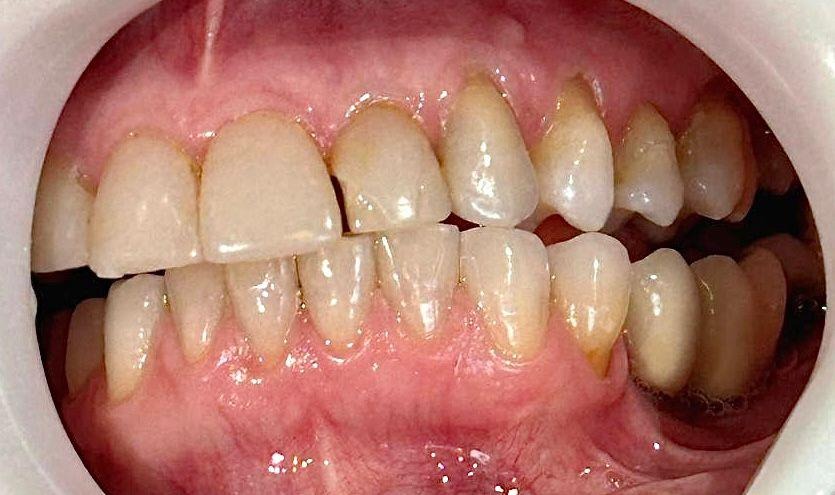

A coleta de dados foi iniciada com a realização de uma consulta inicial, na qual foi conduzida uma anamnese detalhada para levantamento do histórico médico e odontológico do paciente, bem como de suas principais queixas e expectativas em relação ao tratamento estético proposto. Em seguida, foi realizado um exame clínico minucioso com o objetivo de avaliar as facetas previamente instaladas, observando critérios como adaptação marginal, integridade do material restaurador e condições periodontais adjacentes. A saúde bucal geral do paciente também foi analisada nesta etapa, no aspecto inicial foi observado o acúmulo de biofilme causado pela má adaptação cervical, retração gengival, trincas e fraturas derivadas da oclusão desbalanceada, conforme apresenta a figura 1,2,3 e 4.

Figura 3: Vista do lado superior esquerdo.